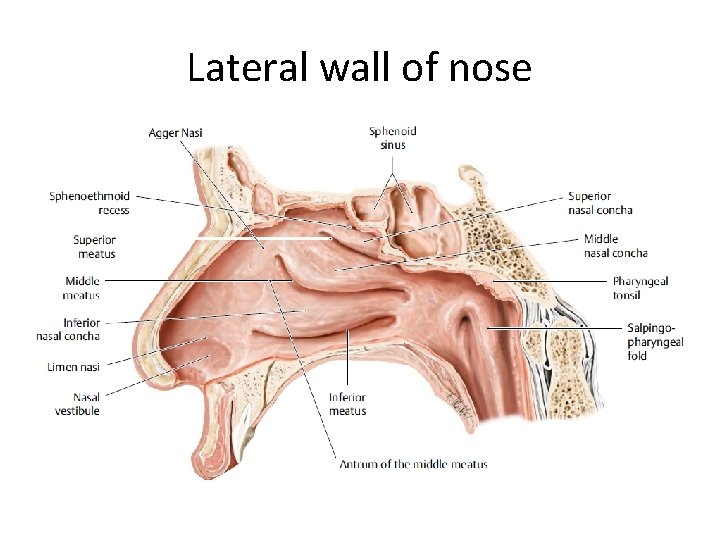

Lateral wall of nose

• Lateral wall is marked by three bony projections called turbinates or conchae • superior (part of ethmoid), • middle (part of ethmoid), • inferior (separate bone).

• Sometimes a fourth turbinate concha suprema may also be present. • Below and lateral to each turbinate is a corresponding meatus

• Inferior meatus- nasolacrimal duct opens in its anterior part. • Middle meatus- consists of bulla ethmoidalis, hiatus semilunaris, infundibulum. • Frontal, maxillary and anterior ethmoidal sinuses open into middle meatus.

• Superior meatus- posterior ethmoidal sinuses open into it. • Sphenoethmoidal recess- triangular fossa above the superior meatus. Sphenoidal sinus opens into it.

• OSTEOMEATAL COMPLEX • The middle meatus is the space below and lateral to the middle turbinate, and is often functionally referred to as the osteomeatal complex. • It contains the drainage pathways for the anterior ethmoids, the maxillary and the frontal sinuses.

• Bulla ethmoidalis • one of the most constant and largest of the anterior ethmoid air cells. • Hiatus semilunaris- hiatus semilunaris is a crescent shaped gap between the posterior free margin of the uncinate process and the anterior wall of the ethmoid bulla

• Ethmoidal infundibulum – • funnel-shaped passage through which the secretions from various anterior ethmoid cells, the maxillary sinus, and, in some cases, the frontal sinus are transported or channeled into the middle meatus.